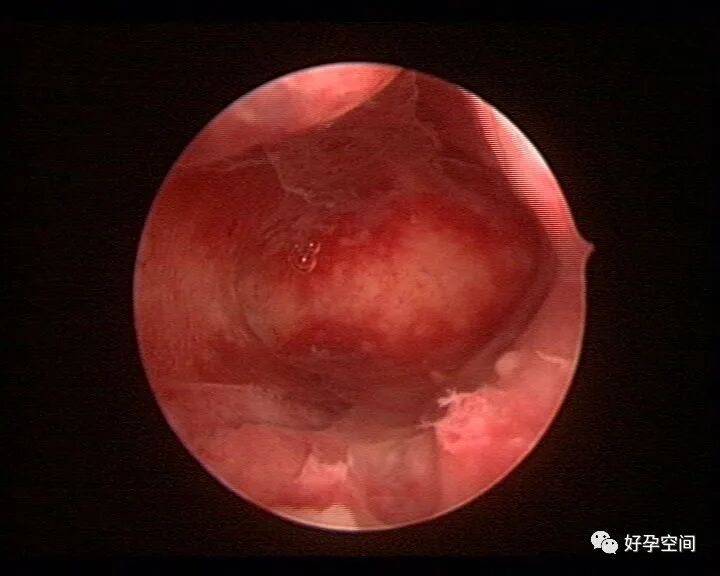

病例20:宫腔粘连变形狭窄内膜瘢痕及出血